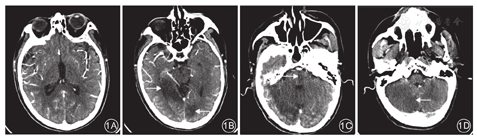

患者术前均进行CTA pc-ASPECT评分。由两名神经内科医师分别对患者的CTA影像资料进行盲法评分,意见不一致时经协商决定最后结果。该CTA pc-ASPECT评分中,总分为10分,左右两侧丘脑、小脑以及大脑后动脉供血区的每一早期缺血性改变分别减1分,中脑或桥脑任何区域的早期缺血性改变减2分。早期缺血性改变定义为CTA源影像上的低密度灶或灰白质模糊区。典型病例见图1。